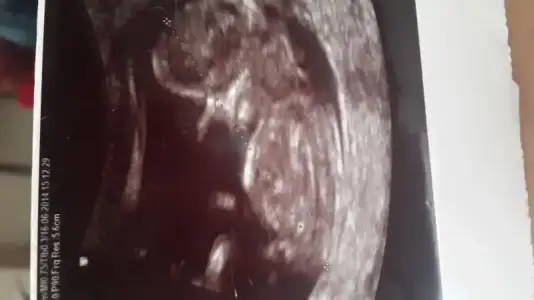

4 boyutluda cok belli alin sekli mesela

Fananaycım bunada yorum yapabılırmısın bu arkadasımın bebegının fotosu